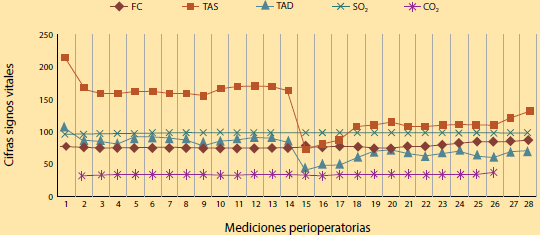

Masculino de 67 años con diagnóstico de para ganglioma vesical. Detectado cuatro meses antes de su intervención por presencia de hematuria macroscópica, sin otros síntomas acompañantes (figuras 1a y 1b). Diabético de larga data con neuropatía periférica tratado con hipoglicemiantes orales y gabapentina. Hipertensión arterial tratada con ARAII (losartán) en aparente control. Fue hospitalizado para preparación y solicitado para cistectomía parcial más resección de tumoración. Valoración y ajuste de tratamiento por el servicio de endocrinología, sustituyendo antihipertensivo ARA II por alfa 1 antagonista (Prazosin 1 mg cada 12 horas), y esquema de insulina. Durante su valoración preanestésica, se encontró descontrol glucémico presentando glucosa de 280 miligramos por decilitro, con ajuste de tratamiento. Signos vitales dentro de parámetros aceptables. Clasificación de riesgo por estado físico ASA III.

Imágenes de los estudios: Cortesía del autor

Figura 1 a) Resonancia magnética y b) tomografía axial donde se observa la presencia de tumoración (paraganglioma) localizado en la vejiga.

Al ingresar al área de recuperación, mostró cifras tensionales elevadas de hasta 213/107 mm/Hg, y se inició infusión intravenosa de Isosorbide 1 mg/h. Se obtiene normalización de la tensión arterial y se procede a la realización de intervención quirúrgica.

En el transcurso de la cirugía mantuvo cifras tensionales con tendencia a elevación, pero con respuesta adecuada a infusión de Isosorbide en rangos de 1.2 a 1.6 mg/h, potenciados con Sevofluorano 2.5 a 4 volúmenes por ciento. Posterior a la extracción de tumoración, presentó disminución importante de la tensión arterial que llegó a 70/40 mm/Hg, se inició con reanimación mediante la administración de 4 bolos de 10 mg de efedrina, en un periodo de 1 hora, y mostró estabilidad posterior. Las mediciones de glucemia capilar periódicas presentaron 120 mg/dl como promedio. Extubación sin eventualidades. Estancia en unidad de cuidados postanestésicos con estabilidad hemodinámica, sin medicamentos de soporte. Egreso de unidad de cuidados postanestésicos sin alteraciones del sistema cardiovascular, ni terapéutica vasopresora. Vigilancia postquirúrgica de signos vitales sin alteraciones hemodinámicas (figura 2).